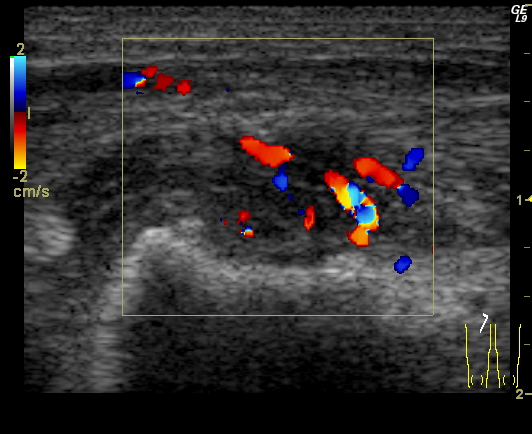

Malrotation-volvulus. During the normal development of the intestinal tract, the intestinal loops make three 90 degree clock-wise rotations around the mesenteric superior artery (MSA.) If this rotation only partially occurs during the embryonic development the intestines remain in a non-rotational or malrotational position, the mesenteric root will be shorter and the cecum will be weakly attached. This anatomic positioning can be symptom free throughout a lifetime, but it predisposes for volvulus. Volvulus can occur at any age, but it is most frequent in the first months of life, when it abruptly occurs with acute bilious vomiting. In this state the intestines around the mesenteric root twist, end up in a complete obstruction that can lead to a rapid death of the intestines. Ultrasonography can depict the mesenteric superior vein (MSV) coiled up around the MSA, so called “whirlpool”-sign.

14. “Whirlpool” sign The mesentery and the superior mesenteric vein, as it coils around the superior mesenteric artery. Volvulus. US exam.